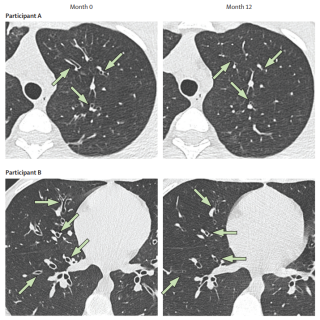

Menée dans 33 centres de référence pédiatriques de la mucoviscidose en France, cette étude a suivi 320 adolescents âgés de 12 à 18 ans ayant initié un traitement par ETI dans le cadre des soins courants. En utilisant la tomodensitométrie thoracique (scanner) à faible dose comme critère principal d’évaluation, les auteurs ont cherché à déterminer si la restauration de la fonction CFTR pouvait modifier l’histoire naturelle des anomalies structurales pulmonaires, en particulier les dilatations bronchiques.

Après un an de traitement par ETI, l’étude met en évidence des améliorations marquées et durables de la fonction respiratoire, de l’état nutritionnel, de la qualité de vie et des marqueurs inflammatoires. De manière notable, les analyses des scanners thoraciques montrent une diminution significative des bouchons muqueux, de l’épaississement de la paroi bronchique et des dilatations bronchiques. Chez une proportion importante de patients, des bronches initialement modérément ou sévèrement dilatées ont partiellement régressé vers des stades moins avancés, voire vers des dimensions normales. Ces améliorations structurales sont étroitement corrélées à une diminution de l’inflammation des voies aériennes, évaluée à partir de biomarqueurs pro-inflammatoires dans les expectorations.

En démontrant que les dilatations bronchiques peuvent être réversibles chez des adolescents traités par ETI, ce travail remet en question l’idée longtemps admise selon laquelle ces lésions pulmonaires seraient irréversibles dans la mucoviscidose. Au-delà de ses implications cliniques immédiates, cette étude apporte des éléments clés sur la manière dont la restauration de la fonction CFTR peut modifier l’évolution de la maladie pulmonaire liée à la mucoviscidose et soutient l’intérêt d’une initiation précoce des thérapies modulatrices du CFTR hautement efficaces.